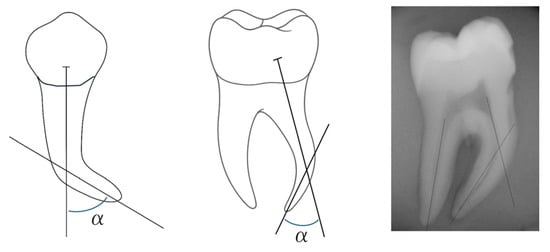

Nickel-titanium (NiTi) usage is associated in endodontics with some complications including canal transportation. Centering ability of a NiTi file is the ability to stay centered in the root canal system during instrumentation. Any undesirable deviation from the natural canal path is indicated as [...] Read more.